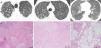

Patient's parenchymal lung disease – imaging and lung biopsy. (A) Chest CT images with interlobular thickening pattern with reticulation, micronodulation and small scattered areas of ground-glass and lobular opacities. Alveolar proteinosis depicted by diffuse alveolar flooding by eosinophilic proteinaceous material, chronic lymphocytic infiltrate and septal fibrosis with collagen deposition.

He underwent a multiple-lobe surgical lung biopsy, which was suggestive of alveolar proteinosis with some fibrotic trace. It revealed aspects of diffuse alveolar occupation by eosinophilic, Periodic-Acid-Schiff positive proteinaceous material, with a light macrophagic reaction, together with abnormal lobular architecture, diffuse septal fibrosis with focal collagen deposition and some multinucleate foreign body giant cells with cholesterol crystal clefts (Fig. 2). There were no granulomas.